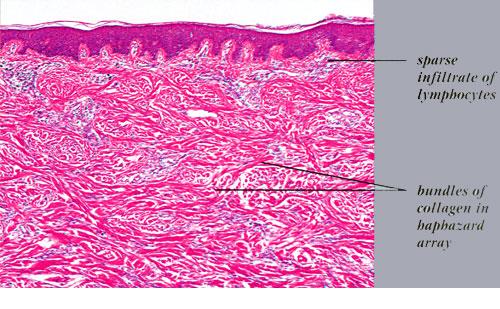

The histologic picture found in the papules in scleromyxedema resembles that observed in lichen myxedematosus. In the diffusely thickened skin, there is extensive proliferation of fibroblasts throughout the dermis associated with irregularly arranged bundles of collagen. In many areas, the collagen bundles are split into individual fibers by mucin. As a rule, the amount of mucin is greater in the upper half than in the lower half of the dermis.